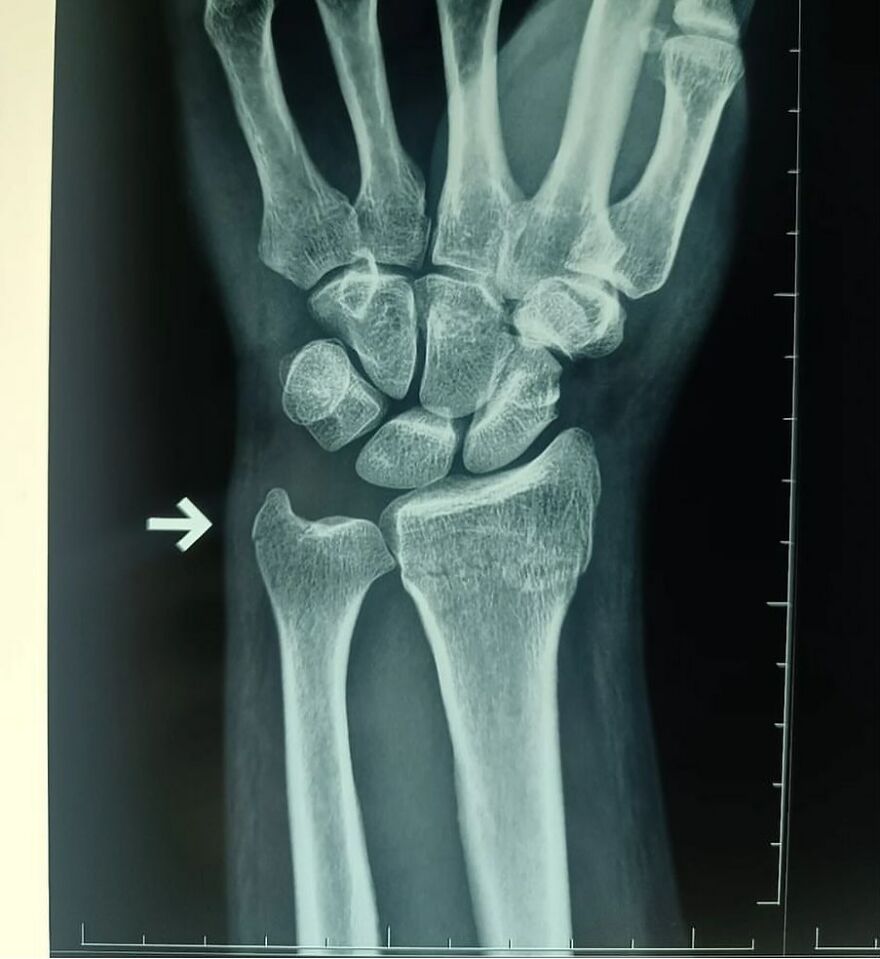

Plain radiograph of wrist joint shows polydactyly with duplication of ulna, duplication of ulnar side of carpal bones, metacarpals and phalanges, absence of radius and absence of thumb. Eight triphalangeal digits are seen. The middle phalanx of medial index finger is hypoplastic